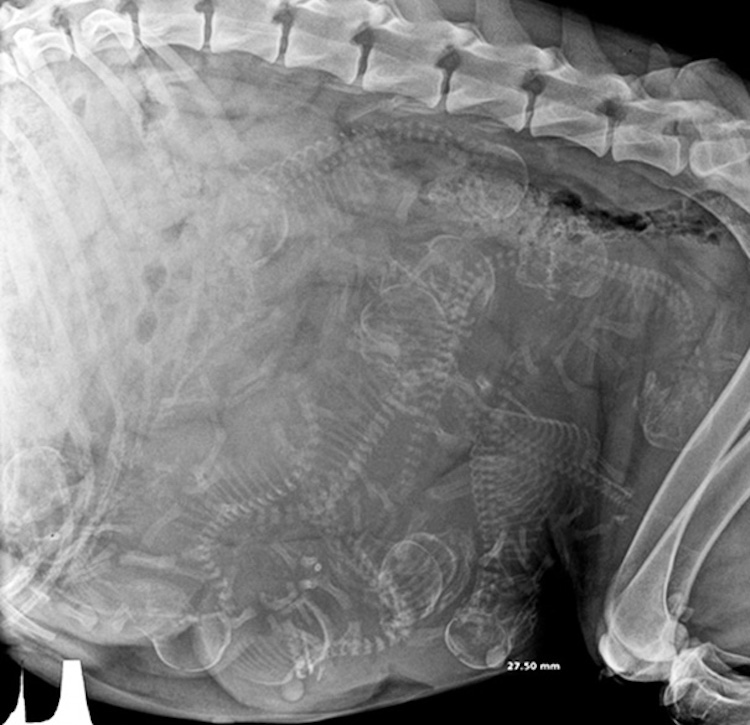

5 – Chienne enceinte. Comme les femmes, les chiennes sont enceintes pendant trois trimestres-chaque 21 jours de long. Autour de 45 jours, il est possible de déterminer au rayon-x combien de chiots feront partie de la portée.